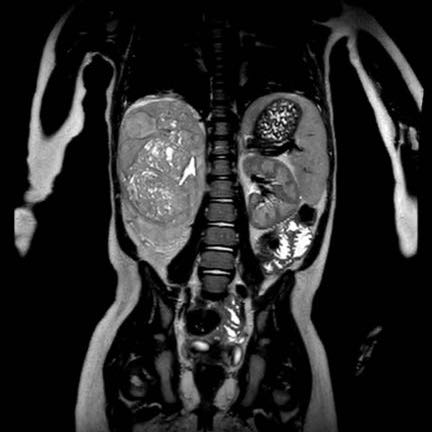

Hình ảnh MRI này của bé gái ba tuổi có khối u thận phải.

Cuộn xem qua các lát cắt chuỗi xung T2W mặt phẳng coronal.

Có một huyết khối u lớn lan từ tĩnh mạch thận vào tĩnh mạch chủ dưới (mũi tên).